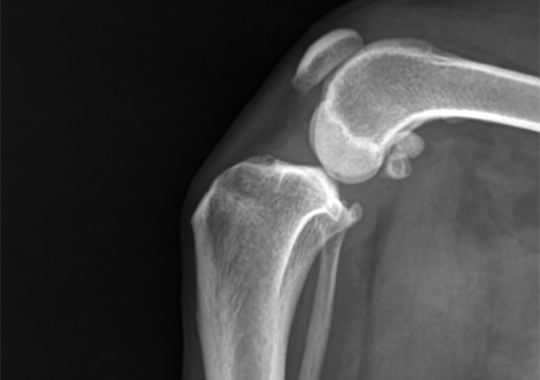

양측 4등급 슬개골 탈구 교정 (DFO) 및 좌측 십자인대 교정

정형외과 케이스

본원은 실력 있는 전문 의료진과 최첨단 시설로 정형외과에서 좋은 예후들을 보여드리고 있습니다. 강아지에게서 쉽게 발생하는 슬개골 탈구, 십자인대 단열 뿐 아니라 다양한 고난도 케이스를 다루고 있으며, 특히 골절 수술은 회복률이 높고 타원 수술 후, 유합부전으로 본원에 내원하여 재수술에 성공한 사례가 많습니다.